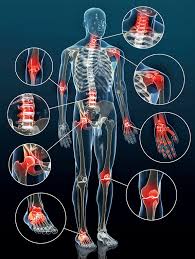

Bei Arthrose im Knie hilft eine Kombination mehrerer Therapien. Welche Medikamente helfen bei Kniearthrose. Medikamente die richtige Ernährung Sport sowie Bandagen und Orthesen versprechen Besserung.

Dabei kommen Physiotherapie physikalische Behandlungen wie unter anderem. Zu diesen Mitteln gehören unter anderem Diclofenac und Naproxen. Wer unter einer Kniearthrose leidet sollte aktiv werden.

Vorrangig geht es dem Orthopäden. Starke trainierte Muskulatur hält das Kniegelenk in der richtigen Position. Doch auch wenn eine Gonarthrose bereits diagnostiziert wurde kann deren Verlauf positiv beeinflusst werden.